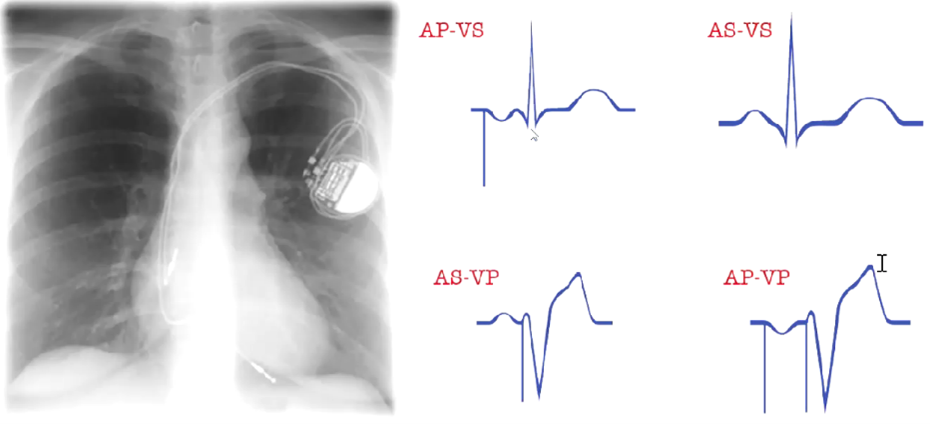

Vad visar bilden?

Pacemaker